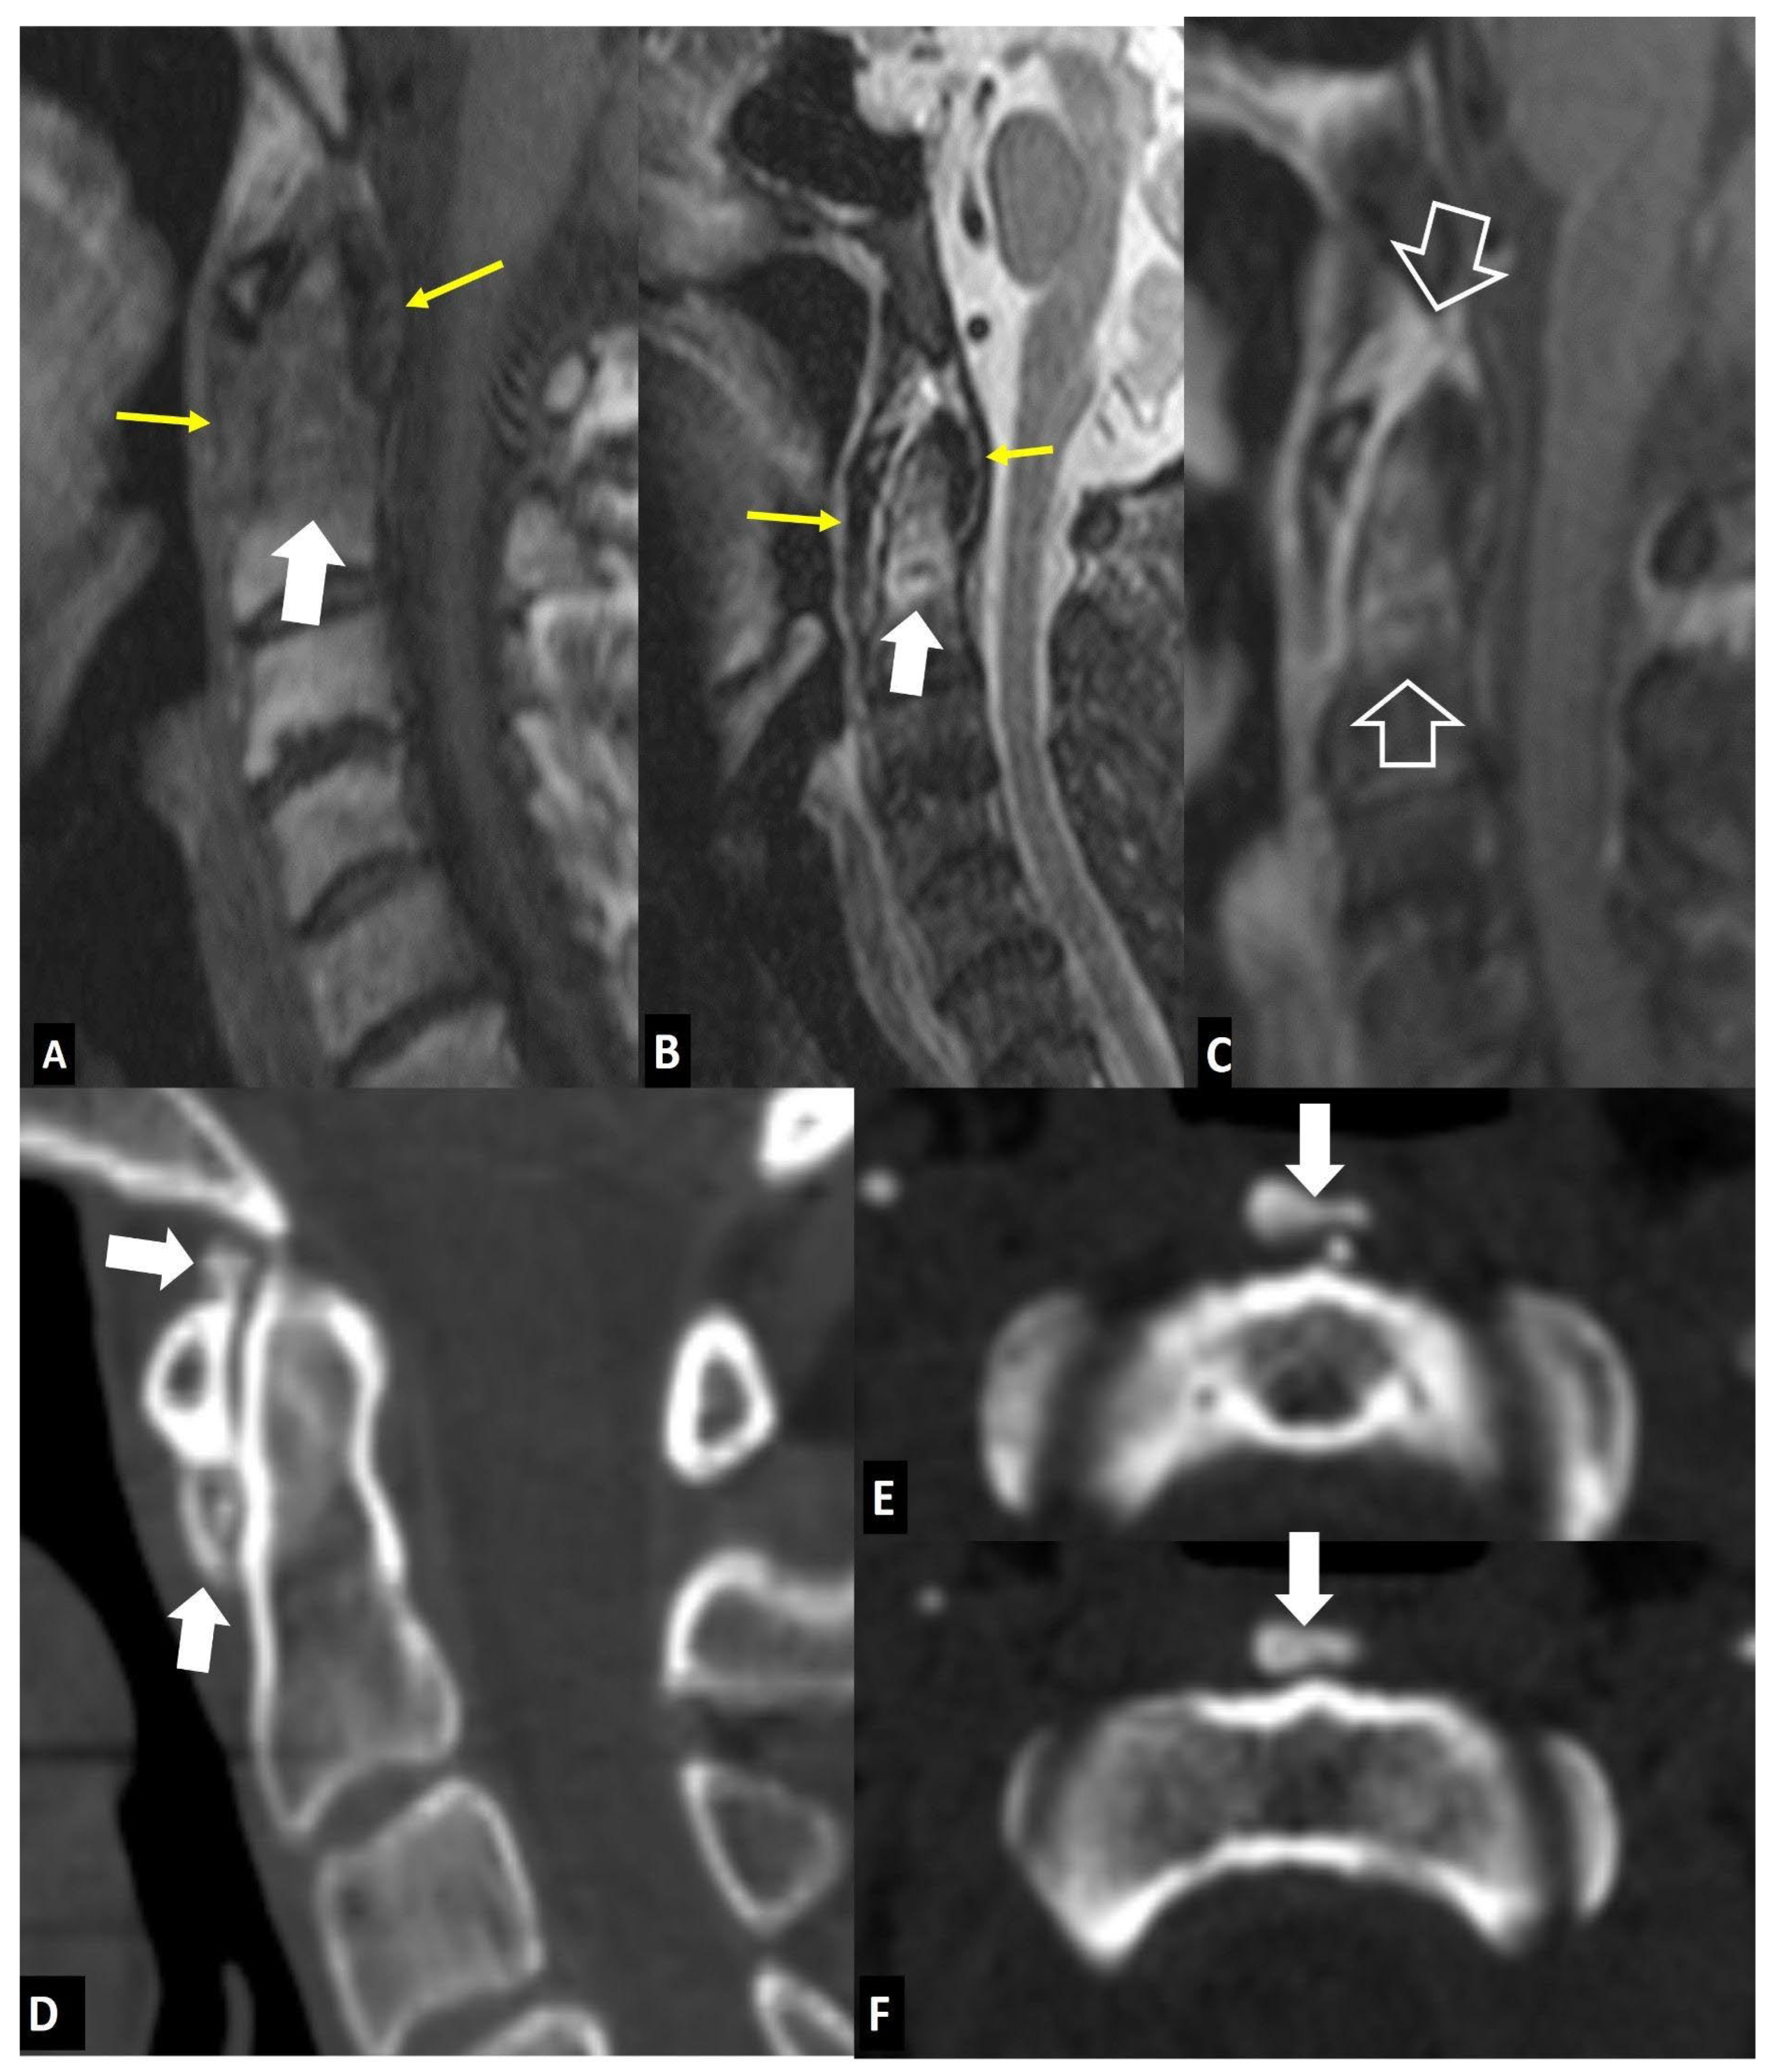

1. a.viii. Rheumatoid Arthritis

1. b. Non Infectious Sacroiliitis